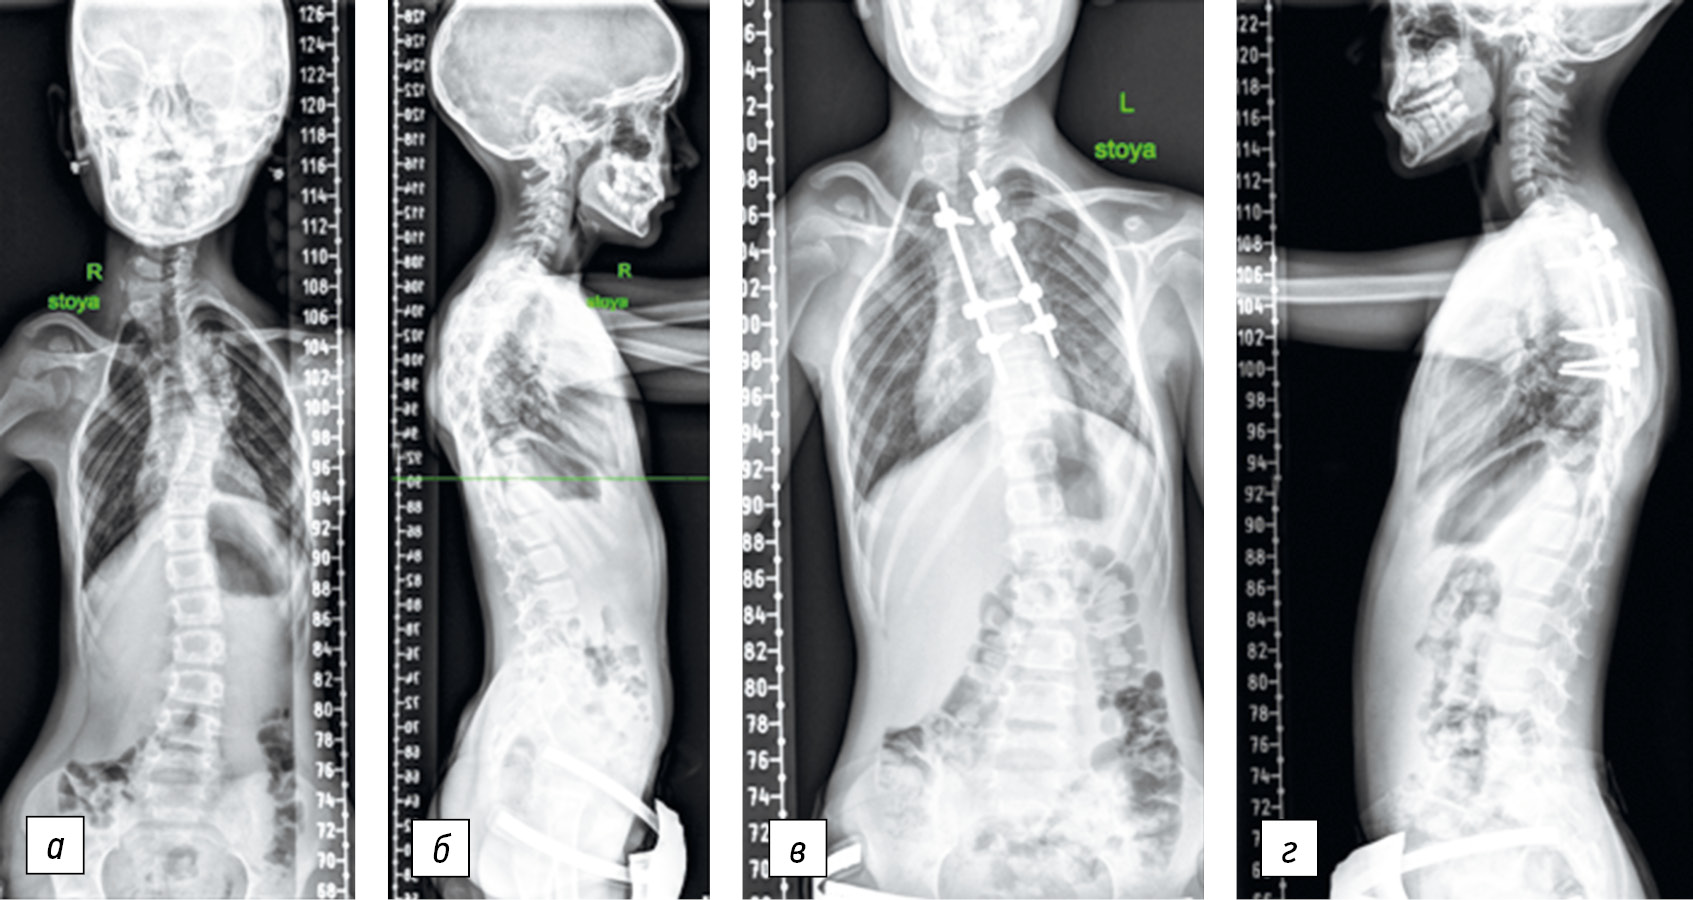

Surgical technique. A skin incision was made from the dorsal approach along the midline in the projection of the spinous processes of the vertebrae; thereafter, the dorsal structures of the vertebrae were skeletonized. Following visual control and radiography using X-ray contrast marks, the vertebrectomy site was determined, i.e., at the level of the apical vertebra. Channels were formed in the bodies of adjacent vertebrae for the installation of pedicle screws. If transpedicular fixation was not possible, laminar hooks were used. Vertebrectomy was started after X-ray control of the correctness of the position of supporting elements. The transverse process of the apical vertebra, a part of the arch on the convex side of the deformity, and a fragment of a rib were removed over a distance of 2.0 cm from the costovertebral joint. Then, wedge-shaped resection of the vertebral body was performed transpedicularly using small curets and conchotomes with the apex facing the concave side of the curvature, while the cranial and caudal bone plates were preserved. Then, the bars bent in accordance with the physiological profile of the spine were fixed in the support elements installed on both sides of the deformity, and segmental correction was performed (Fig. 4). The amount and position of correction of the supporting elements were assessed using intraoperative radiography (Fig. 5). The procedure was completed with spinal fusion using autologous bone, and the wound was drained and sutured.

Fig. 5. Panoramic X-ray of the spine in frontal and lateral projections before (a, b) and after (c, d) surgery. A 9-year-old patient; after corrective wedge osteotomy with correction and stabilization of spinal deformity using a multi-support corrective system